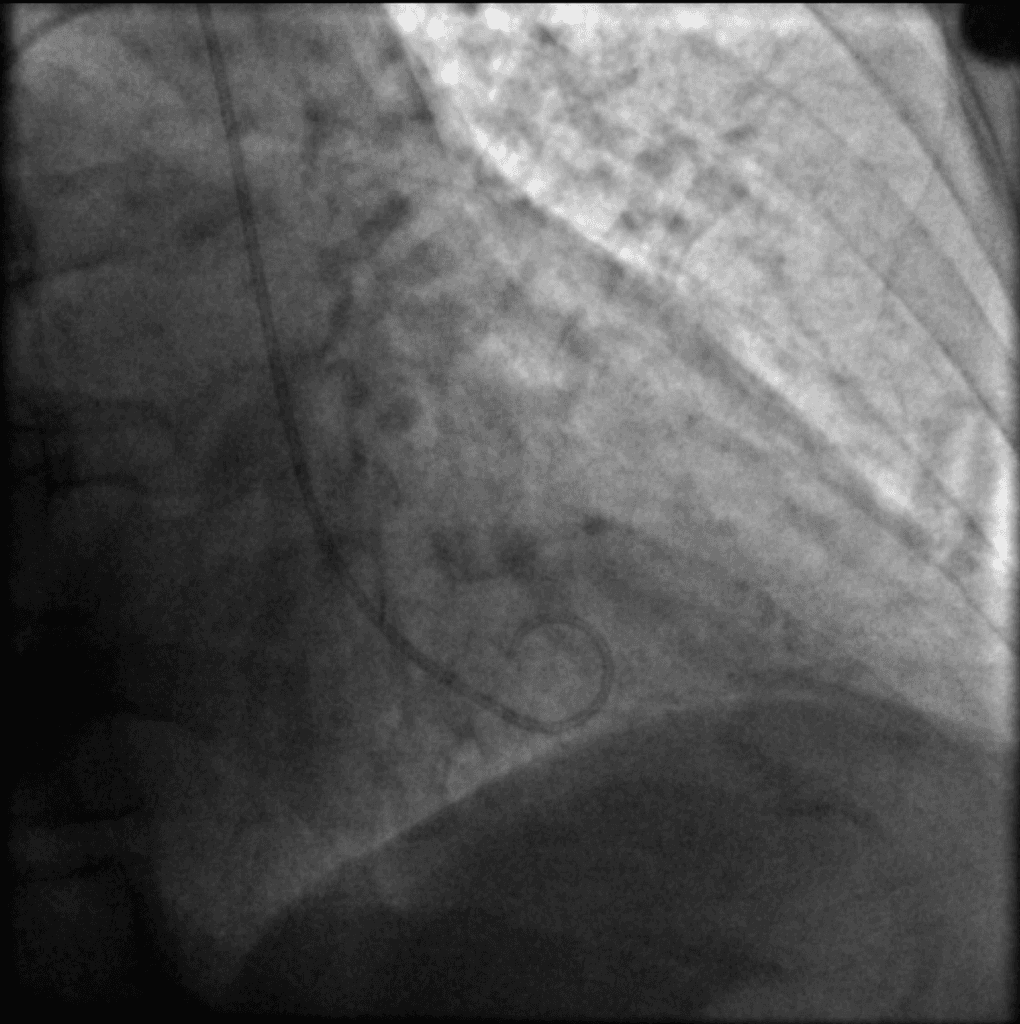

Nghi ngờ phình thất và vỡ thất được kiểm soát trên siêu âm tim qua thành ngực.

- Siêu âm tim qua thành ngực lặp lại sau 4 tuần cho thấy thành trước rối loạn vận động đã hồi phục, tràn dịch màng ngoài tim (pericardial effusion) đã biến mất, đồng thời phân suất tống máu cải thiện.

- Hình ảnh kết hợp với sự hồi phục tự phát và chậm (spontaneous delayed resolution) phù hợp với bệnh cơ tim Takotsubo (tâm phình do stress) (Takotsubo [stress-induced] cardiomyopathy).